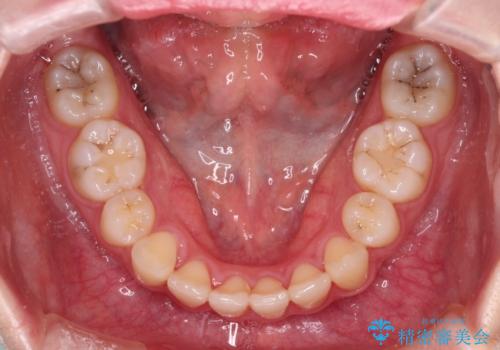

- 地元で抜歯治療を行っている途中、東京へ転職したため治療を継続して欲しいとのことで来院された患者様です。

出っ歯を抜歯矯正にて治療をしていらっしゃいましたが、抜歯スペースが少し残っていたため、閉じて歯列を仕上げていくこととしました。